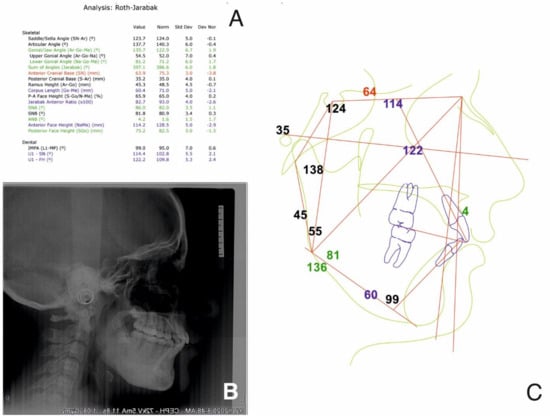

2.2.1. Initial Examination

2.2.2. Treatment Objectives